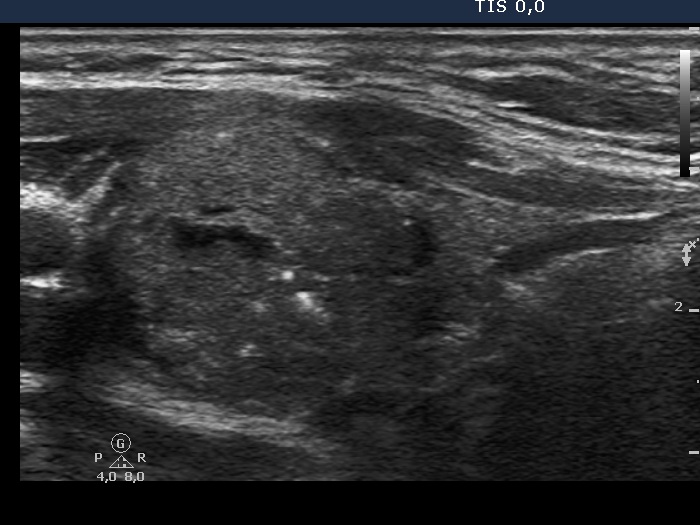

Ultrasonography. The thyroid was echonormal. There was a hypoechogenic nodule with microcalcifications in the right lobe, and another hypoechogenic nodule with microcalcifications and cotton-like patches in the left lobe.

There are larger patch-like hyperechogenic figures in the left, medullary carcinoma focus. These are clearly amyloid deposits. While the relatively smaller and more bright figures are larger than a microcalcification. They are probably also amyloid deposits.